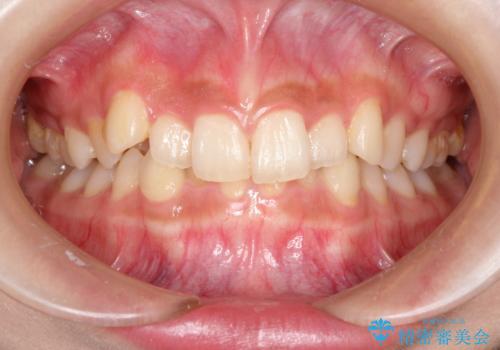

- 前歯のガタガタを主訴に来院された患者様です。

八重歯になっており、下顎の前歯が上顎の前歯に隠れてしまう、ディープバイトという状態でした。

インビザラインを使用して矯正する計画としました。